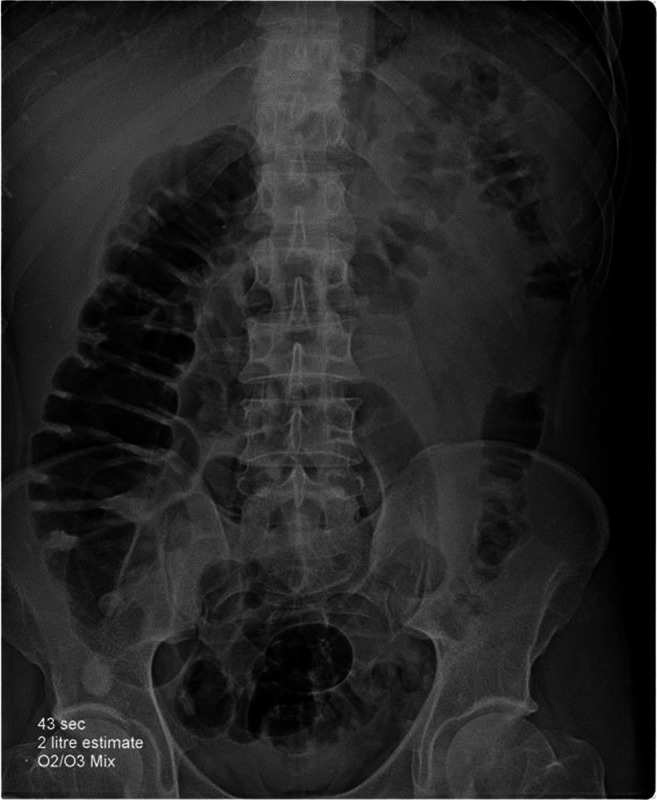

A 60-year-old female hypertensive patient, obese with body mass index 30 kg m−2, was confirmed COVID-19 positive. She was home quarantined for 6 days. On day 7, the patient presented to the emergency room with fever, dyspnea, and tachypnea. Initial assessment showed temperature: 38 °C; respiratory rate (RR): 50 cycles min−1; heart rate (HR): 120 beats min−1; and arterial oxygen saturation (sPO2): 60% on room air. After the failure of a non-rebreathing face mask to achieve sufficient oxygen saturation, the patient was attached to continuous positive airway pressure (CPAP) in the intensive care unit (ICU) with fraction inspired oxygen (FiO2): 90% with progressive improvement of sPO2 till reaching 90%. A session of rectal O3 therapy was done. Two liters of oxygen-Ozone (O2/O3) gas mixture with a concentration of 12.6 μg mL−1 (25.2 mg) was injected slowly into the rectum by a previously inserted catheter. Abdominal and pelvic X-ray was done and showed gaseous distention of the colon down to the cecum (Fig. 1). After 2 h sPO2 started to improve gradually till reaching 96%, with heart rate slowing down to 95 beats min−1 after 4 h of O3 therapy. After 24 h, the patient was weaned from the CPAP and Venturi face mask, FiO2 60% was applied with sPO2 94%, RR 28 cycles min−1 and HR 90 beats min−1. After 48 h from the first O3 session, we noticed a gradual improvement of the patient, SpO2 was 94% with venturi O2 mask 50%, RR was 28 cycles min−1, and HR 94 beats min−1. Pelvic and abdominal X-ray was repeated and showed an empty colon so we decide to give her another session of O3. The patient started to improve gradually over the next 2 days, and finally, sPO2 was 95%, HR 84 beats min−1, and RR 16 cycles min−1 with supplemental oxygen 28% with Venturi mask. The patient was discharged to the inpatient isolation ward then discharged home by day 16 with no adverse effects.

Fig. 1.

Pelvi-abdominal X-ray after rectal insufflation of 2 L of ozone

Rectal insufflation O3 therapy was used safely with a dose range from 0.2 to 79 mg kg−1 bodyweight, a concentration between 10 and 50 μg, and volume up to 300 mL without reported side effects [19]. With our patients, we used the rectal insufflation method which is more easily applicable, safe, and effective and did not need special training. We found that small volumes did not produce fast improvement of oxygenation so we decided to use a high volume of O3 as tolerated by the patients and guided by X-ray as we believe that this will increase the surface area available for absorption with the probability of better results. Our target was to fill the whole colon with the gas mixture of O2/O3. Improvement of oxygenation in our cases was faster than described in cases that received small volumes of O3 [8]. More research work is needed to determine the best volume and concentration of rectal O3 therapy for patients with COVID-19 pneumonia.